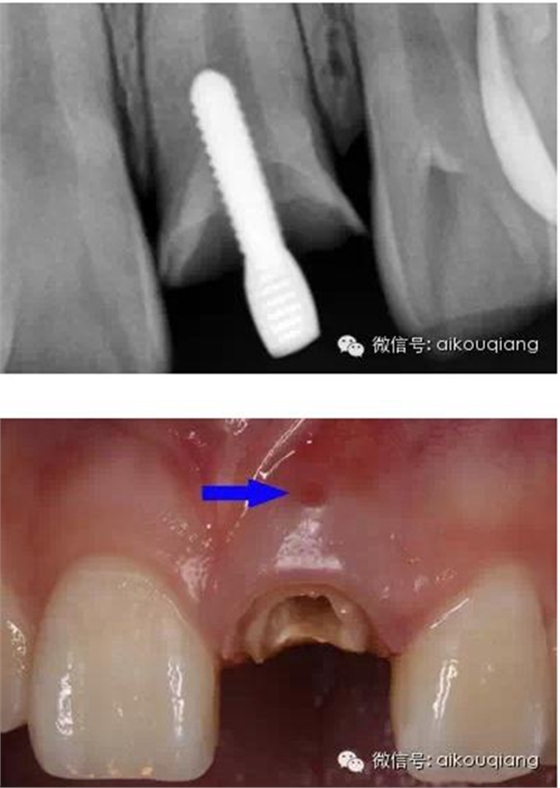

下面是最近處理的一個病例

患者外院螺紋樁核加樹脂冠

唇側(cè)出現(xiàn)瘺管

X片

瘺管部位

瘺管位置